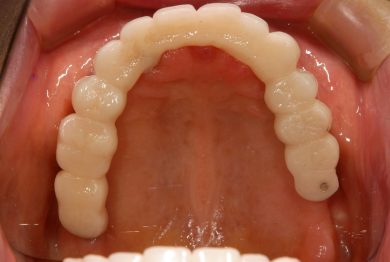

術後18年 下顎臼歯は当初から使えるまで使ってインプラントにしようと話してましたが、今もなんでも咬めるということですので、90歳の今このまま使っていただいています。今後次の治療になる時は、訪問診療ですね。

18年後の補綴。クラシカルですが、十分機能しています。

18年前のインプラント治療が今なお機能し、90歳の患者さんが「なんでも咬める」と笑顔で語ってくださる。